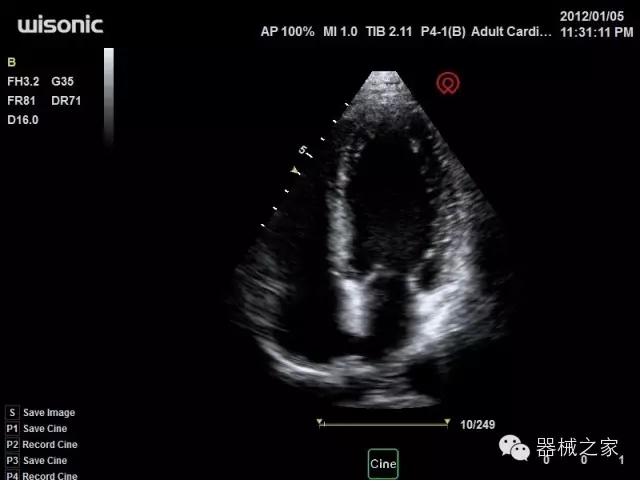

經(jīng)典產(chǎn)品:四葉草

臨床圖片賞析

產(chǎn)品特點(diǎn)

·全球目前唯一一款配備主機(jī)雙探頭接口,整機(jī)重量(含電池)在5公斤以內(nèi)的便攜式彩超;

·一款互聯(lián)網(wǎng)彩超,只要有手機(jī)信號的地方就可以非常方便地實(shí)現(xiàn)遠(yuǎn)程會診和病案調(diào)?。?/span>

·鎂鋁合金外殼,堅(jiān)固可靠耐用;

·獨(dú)有的HoloTM PW 實(shí)時3取樣門PW成像技術(shù),精確進(jìn)行血管診斷;

·一鍵優(yōu)化B、Color、PW,Auto Doppler自動識別血管位置、偏轉(zhuǎn)角度等,提高工作效率;

·30°超廣角精細(xì)偏轉(zhuǎn)成像技術(shù),更優(yōu)異的頻譜圖像;

·W+智能搜索引擎,快速尋找圖像;

·SSD、USB3.0保障開機(jī)快,導(dǎo)出圖像更快,減少等待時間;

·WIFI、網(wǎng)口、3G,多重聯(lián)網(wǎng)方式,全天候保障云端備份,不再擔(dān)心圖像丟失;

CFDA注冊證編號

·粵械注準(zhǔn)201522231208